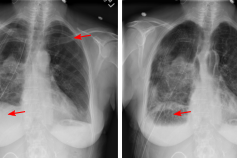

X-ray X-ray is a commonly used low-cost exam for screening and diagnosis. However, X-ray radiographs are 2D representations of 3D structures causing considerable clutter impeding visual inspection and automated image analysis. Here, we propose a Fully Convolutional Network to suppress undesired visual structure from radiographs while retaining the relevant image information such as lung-parenchyma. (Hofmanninger et al. 2019)